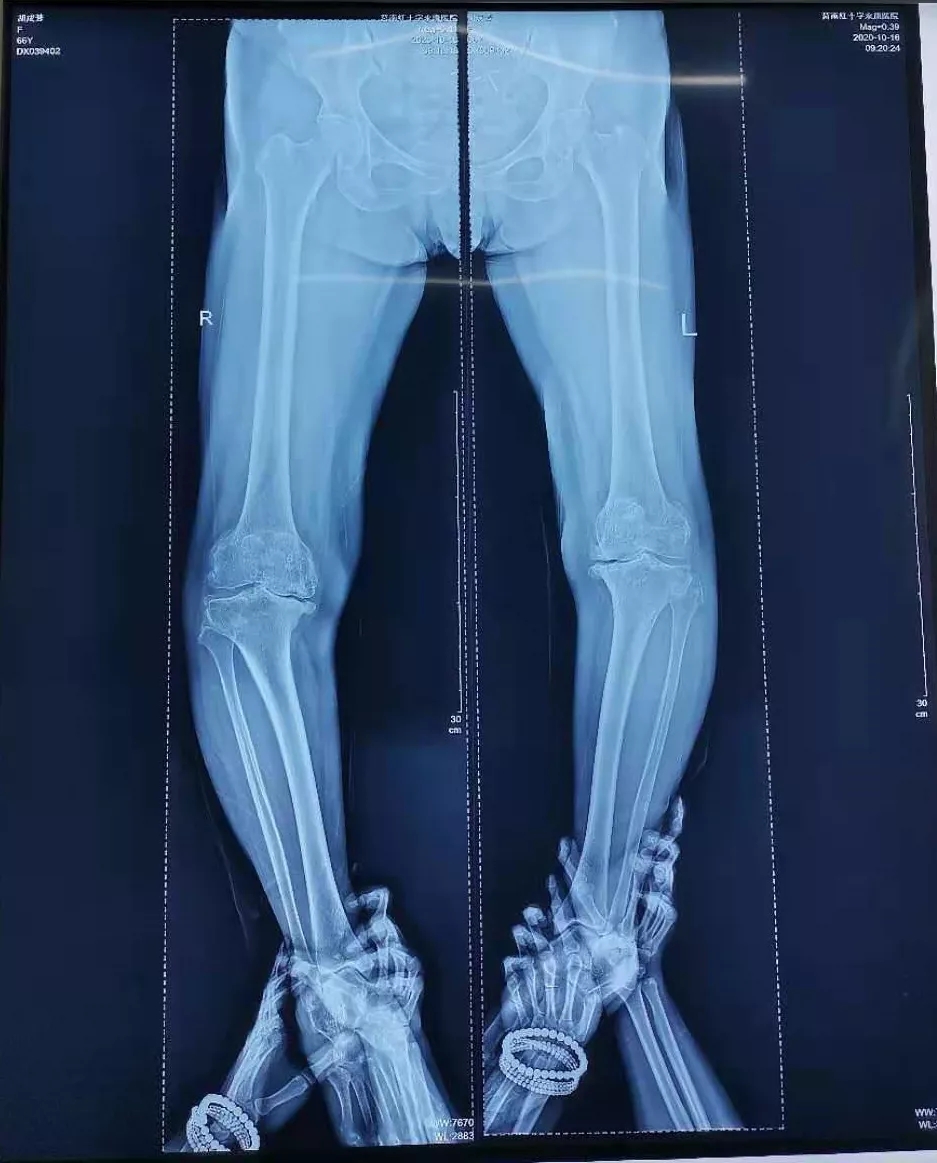

检 查:术前负重位X-ray显示双膝重度骨性关节炎合并屈曲内翻畸形。

术前影像:

术前正位

术中处理:双侧间隔10天手术,均采用股四头肌snip切口入路, 术中患膝屈伸活动可达到0°~90°。术后24小时开始屈伸功能锻炼,术后5天屈伸活动达到0°~90°。

术后影像: